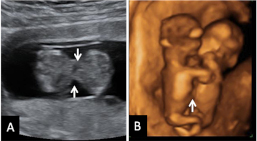

En A se aprecia el hueso nasal (flecha) en una gestación normal de 12 semanas. En B, un embrión de 12 semanas con síndrome de Down, en el que el hueso nasal está ausente y además tiene una translucencia nucal aumentada.

Imagen del hueso nasal ausente (A) y pliegue nucal aumentado (B)